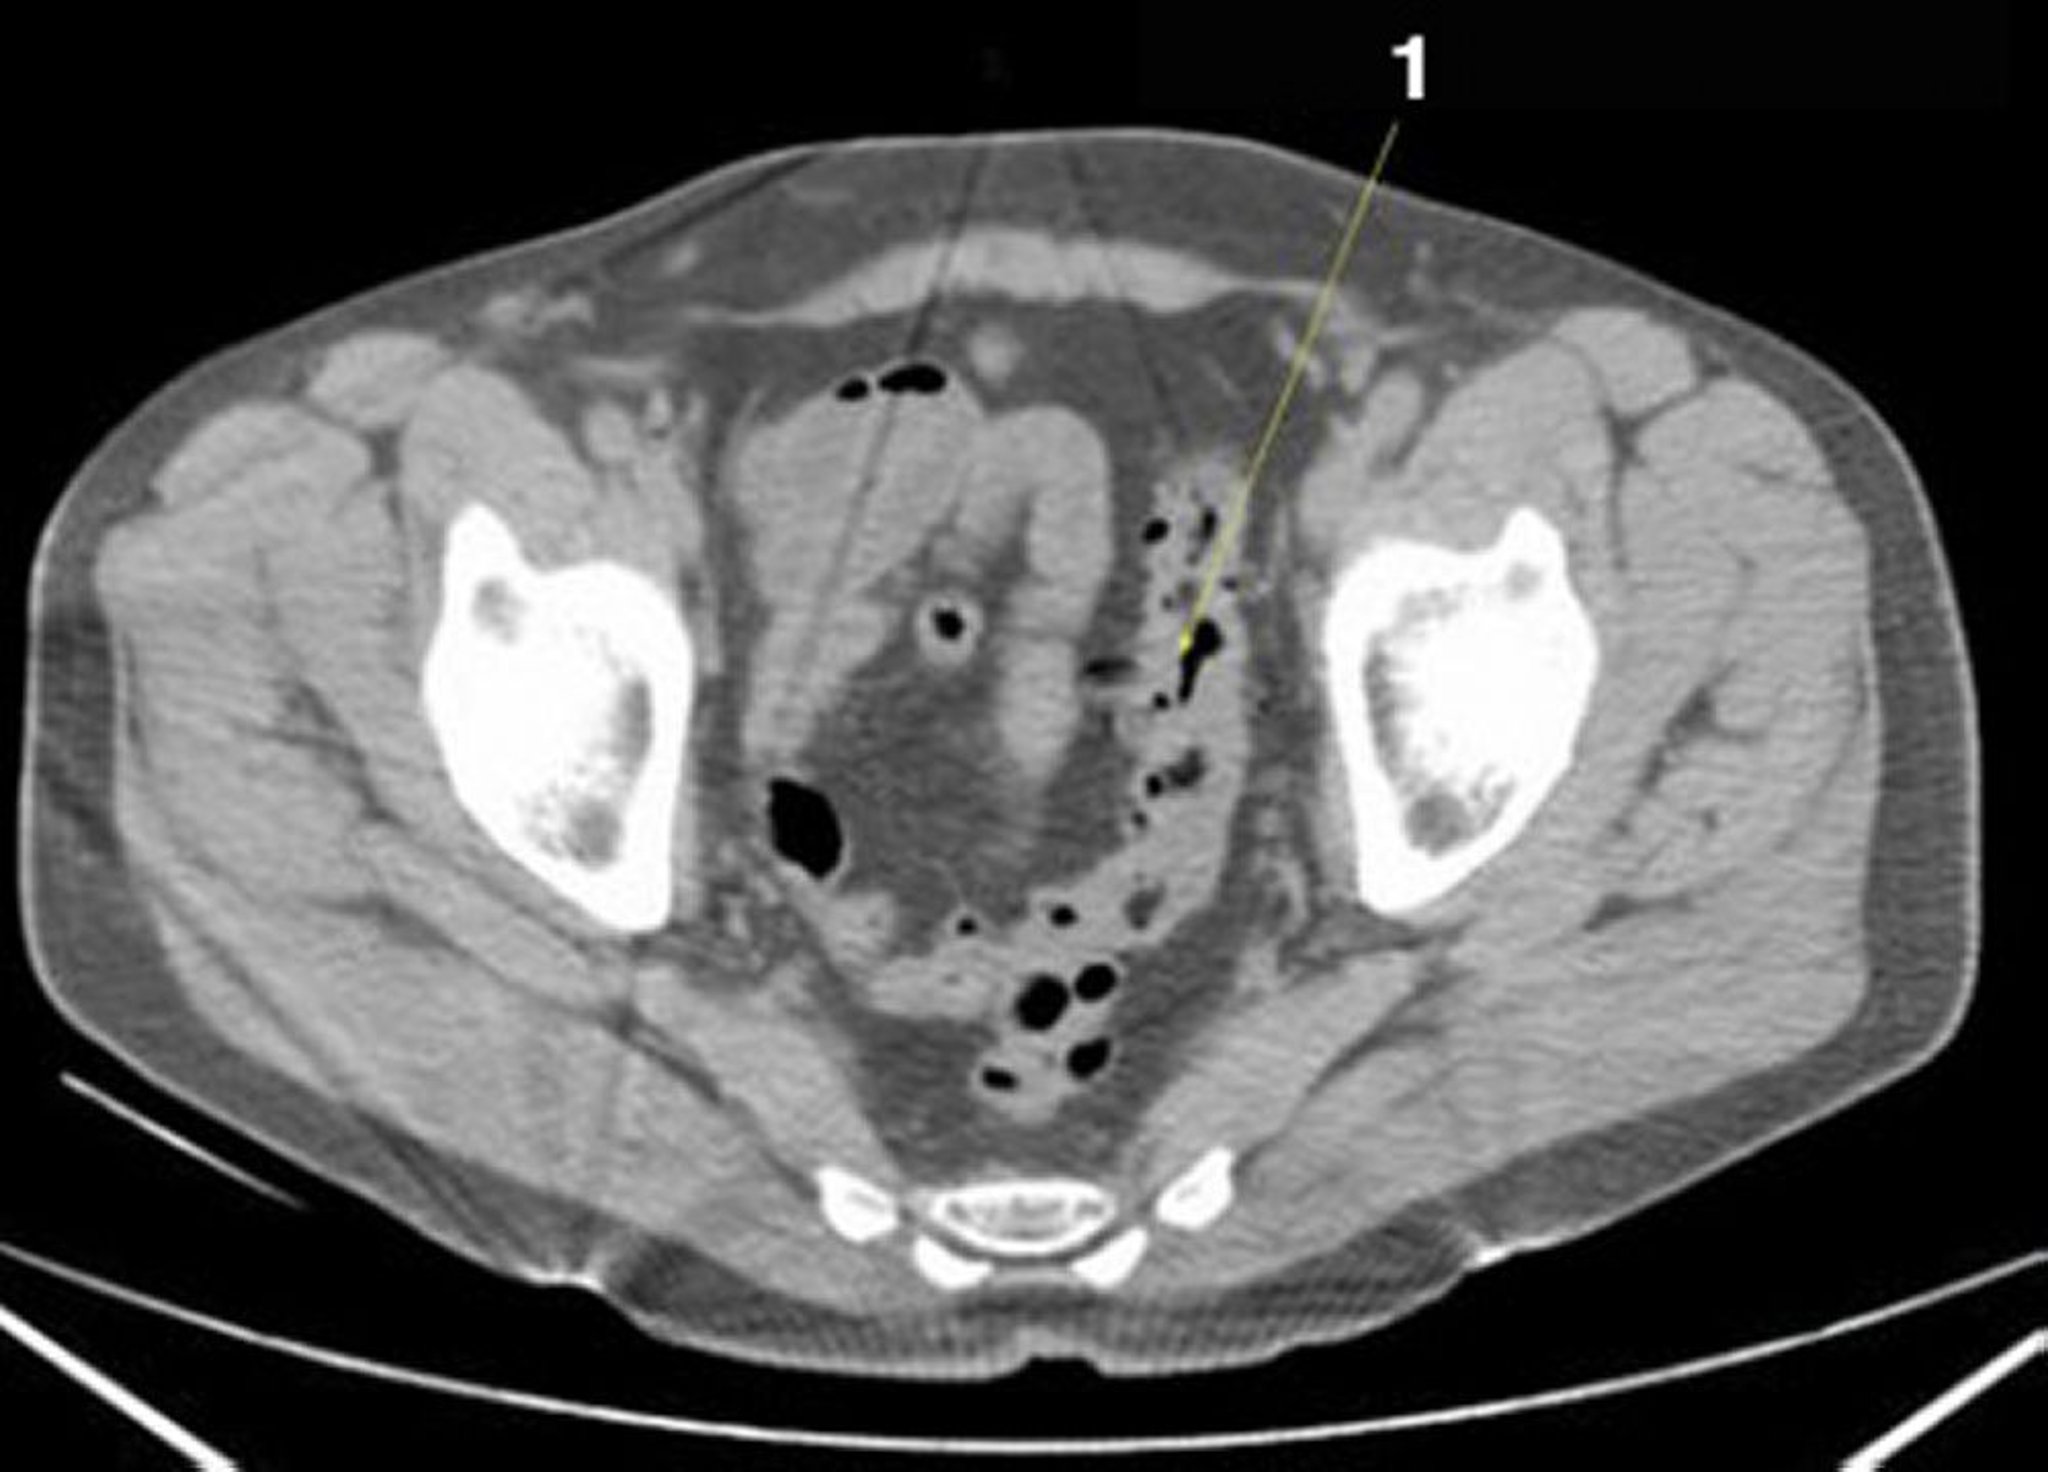

Phim chụp CT vùng bụng và vùng chậu không thuốc cản quang cho thấy giải phẫu bình thường (lát cắt 25)

1 = đại tràng sigma.